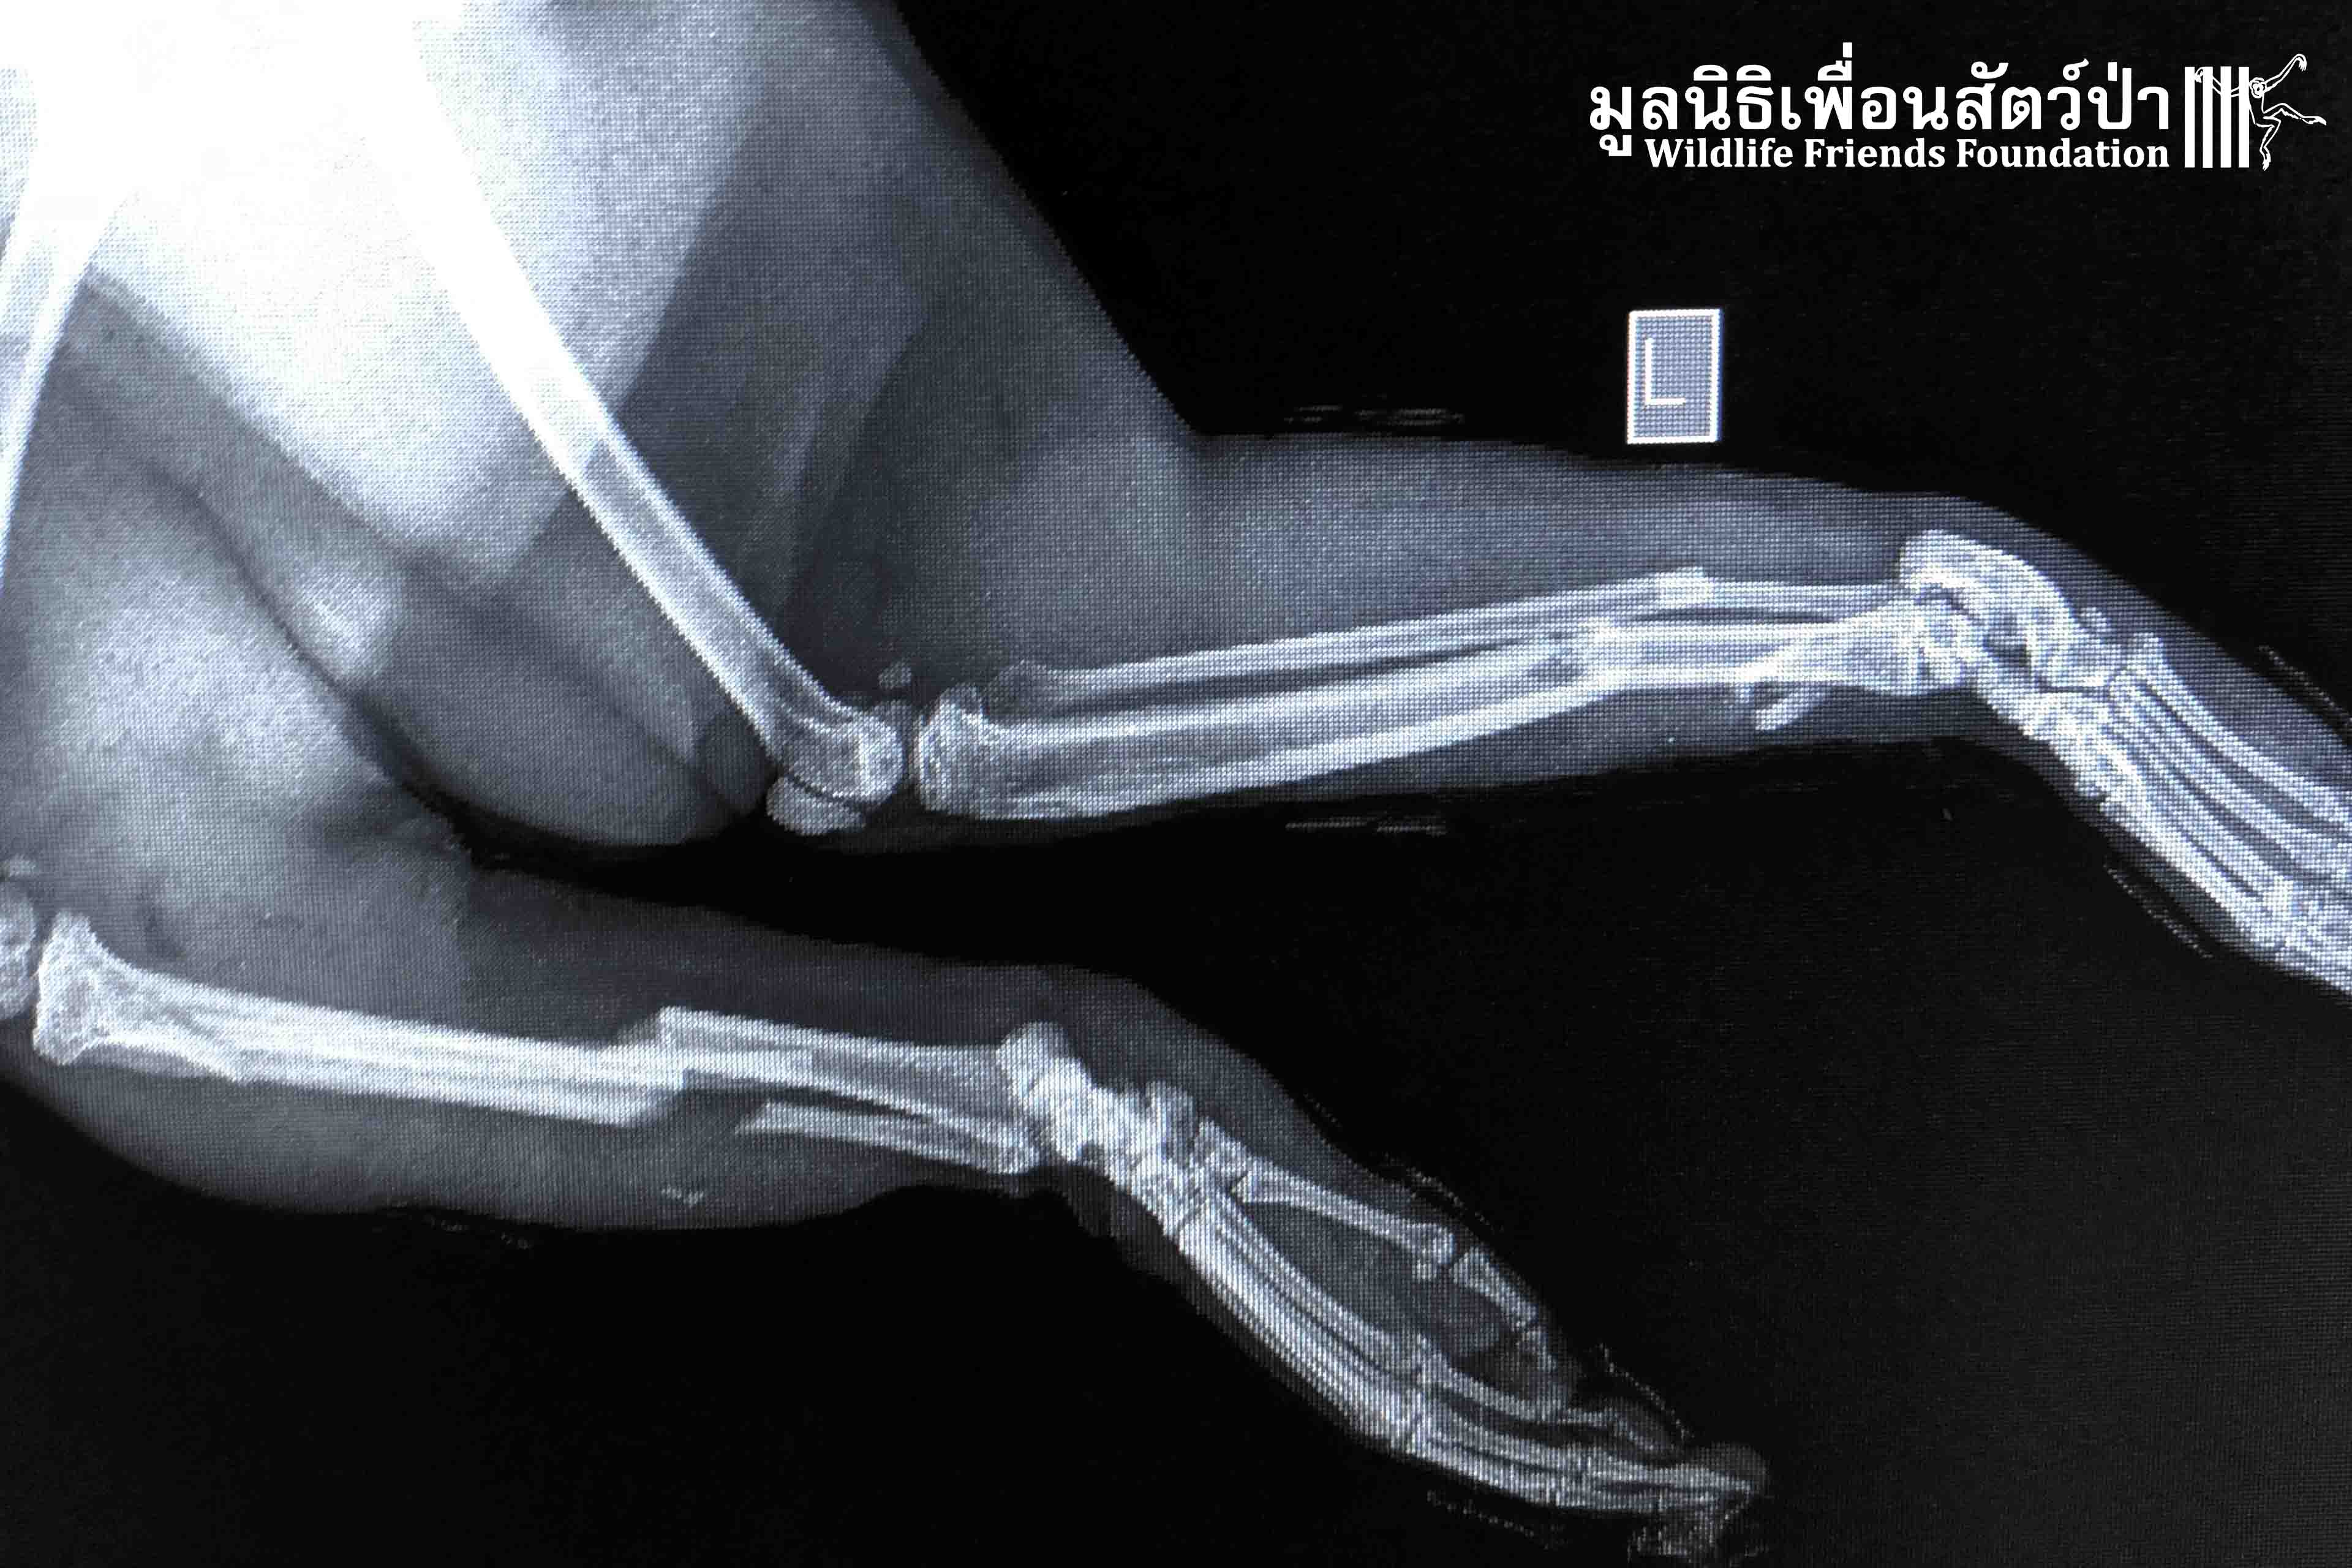

Bad luck for “Leggy” a male long tailed macaque (Macaca fascicularis), who fell 5 meters from a tree branch that unexpectedly broke. His bad luck didn’t end with bruises on his body… Leggy also sustained broken bones in both of his legs, preventing him from moving.

But sometimes bad luck brings good luck as well. A concerned local found Leggy immobile on the ground and contacted us about a monkey in need of emergency medical treatment. Now he is in the good hands of the WFFT vet team, where he will receive the care he needs until he recovers enough to be returned to the wild.